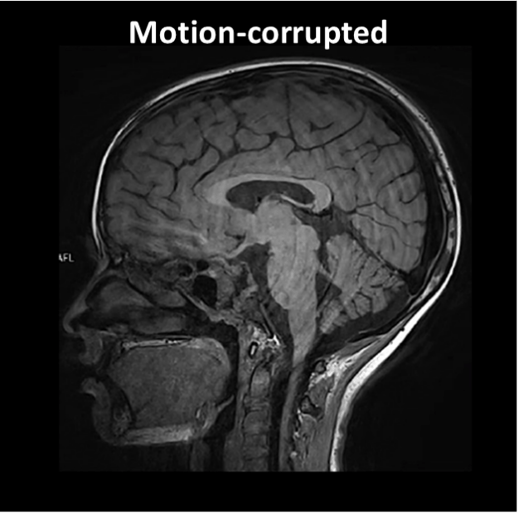

One of the most important is patient motion. Even small movements during acquisition can distort measurements and compromise quantitative accuracy. Motion artifacts are a common reason for degraded image quality and repeated scans.

Figure 4: Technical Pitfalls: Example of a motion-corrupted image. Source: Courtesy of Bac Nguyen.